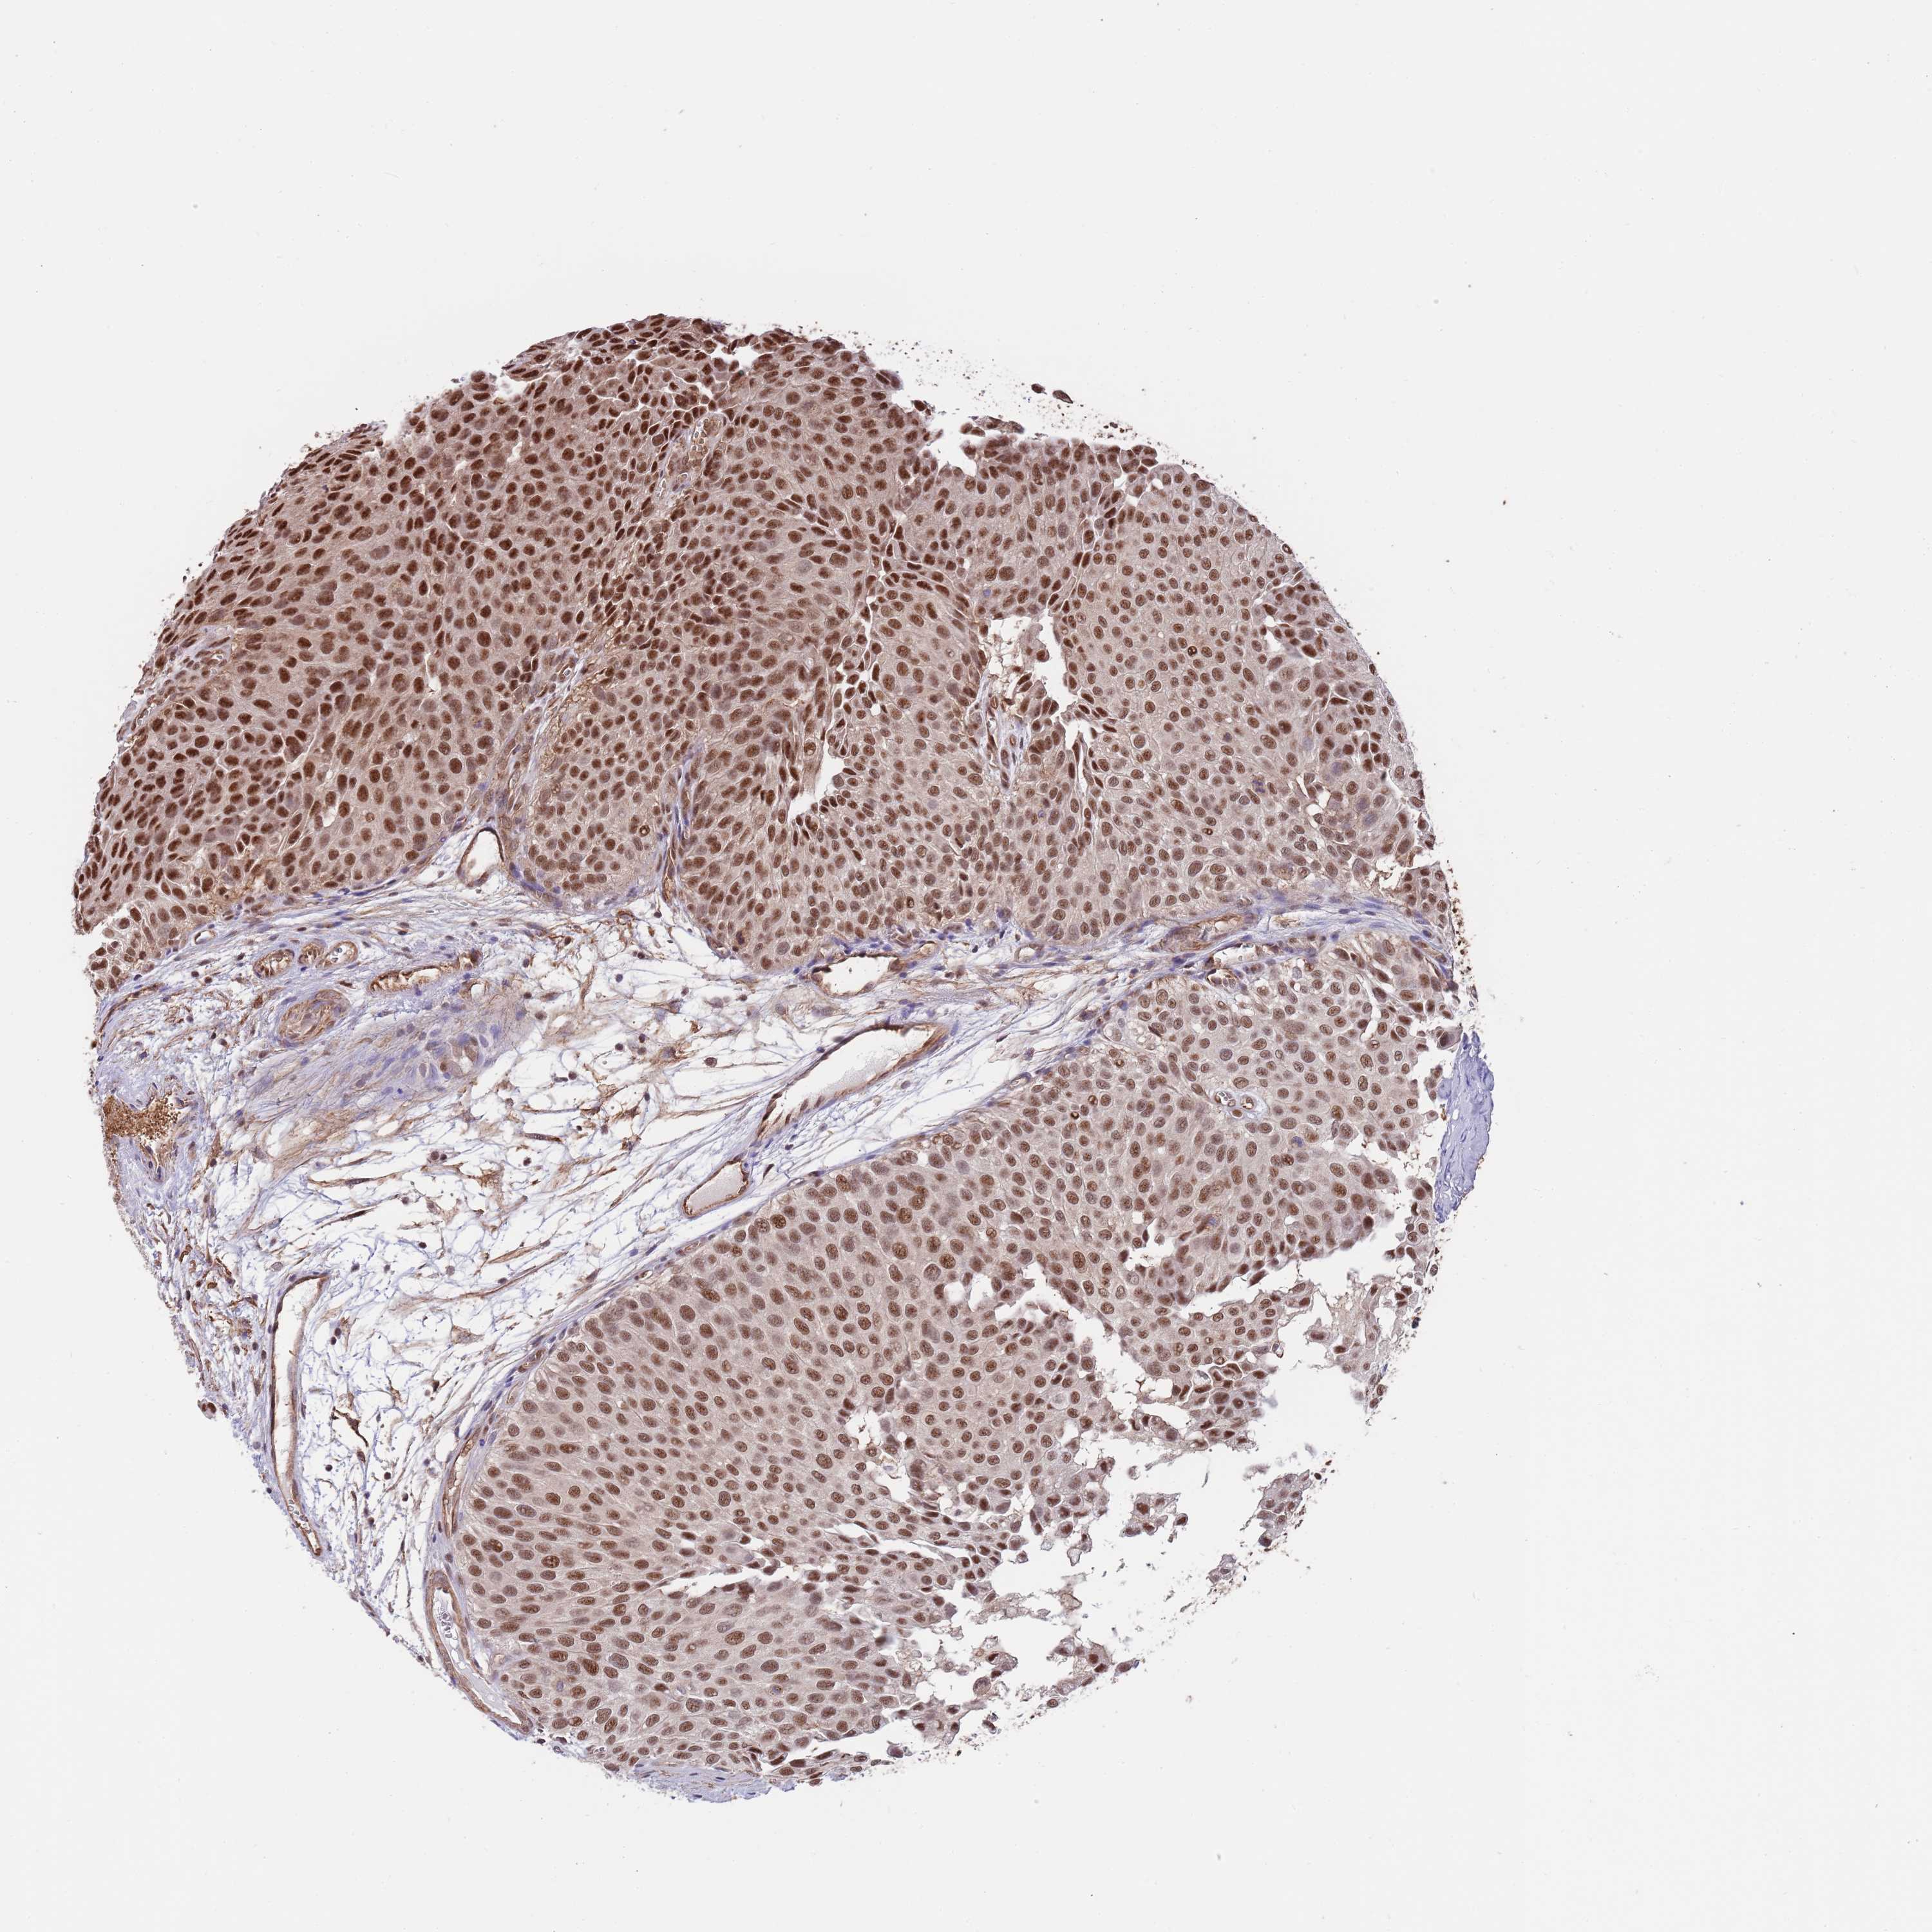

UROTHELIAL CANCER - Protein expressioni

A mouse-over function shows sample information and annotation data. Click on an image to view it in a full screen mode. Samples can be filtered based on level of antibody staining by selecting one or several of the following categories: high, medium, low and not detected. The assay and annotation is described here.

Note that samples used for immunohistochemistry by the Human Protein Atlas do not correspond to samples in the TCGA dataset.

Antibody stainingi

Antibody staining in the annotated cell types in the current human tissue is reported as not detected, low, medium, or high, based on conventional immunohistochemistry profiling in selected tissues. This score is based on the combination of the staining intensity and fraction of stained cells.

Each image is clickable and will lead to virtual microscopy that enables deeper exploration of all samples and also displays staining intensity scores, fraction scores and subcellular localization as well as patient and tissue information for each sample.

Antibody HPA048461

Staining

High

Medium

Low

Not detected

Intensity

Strong

Moderate

Weak

Negative

Quantity

>75%

75%-25%

<25%

None

Location

Nuclear

Cytoplasmic/membranous

Cytoplasmic/membranous,nuclear

Urothelial carcinoma, Low grade

Urothelial carcinoma, High grade

Urothelial carcinoma, NOS